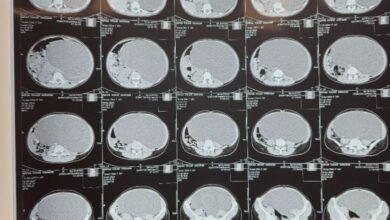

استئصال كيس لمريضة عشرينية

أحوال – زهير جمعه الغزال: استقبلت الطوارئ الجراحية في مدينة الصدر الطبية في العراق في اول أيام عيد الفطر المبارك مريضة تبلغ من العمر 20 سنة تعاني من حالة بطن…